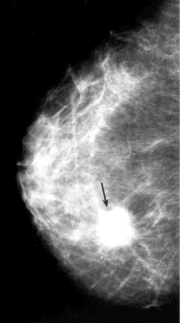

| 16:17, 5 בספטמבר 2012 | Breastcancer2312.png (קובץ) |  |

142 קילו־בייטים | Motyk | 1 | |